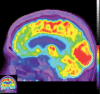

Neurodegenerative diseases are a devastating group of disorders that can be difficult to accurately diagnose. Although these disorders are difficult to manage owing to relatively limited treatment options, an early and correct diagnosis can help with managing symptoms and coping with the later stages of these disease processes. Both anatomic structural imaging and physiologic molecular imaging have evolved to a state in which these neurodegenerative processes can be identified relatively early with high accuracy. To determine the underlying disease, the radiologist should understand the different distributions and pathophysiologic processes involved. High-spatial-resolution MRI allows detection of subtle morphologic changes, as well as potential complications and alternate diagnoses, while molecular imaging allows visualization of altered function or abnormal increased or decreased concentration of disease-specific markers. These methodologies are complementary. Appropriate workup and interpretation of diagnostic studies require an integrated, multimodality, multidisciplinary approach. This article reviews the protocols and findings at MRI and nuclear medicine imaging, including with the use of flurodeoxyglucose, amyloid tracers, and dopaminergic transporter imaging (ioflupane). The pathophysiology of some of the major neurodegenerative processes and their clinical presentations are also reviewed; this information is critical to understand how these imaging modalities work, and it aids in the integration of clinical data to help synthesize a final diagnosis. Radiologists and nuclear medicine physicians aiming to include the evaluation of neurodegenerative diseases in their practice should be aware of and familiar with the multiple imaging modalities available and how using these modalities is essential in the multidisciplinary management of patients with neurodegenerative diseases.©RSNA, 2020.